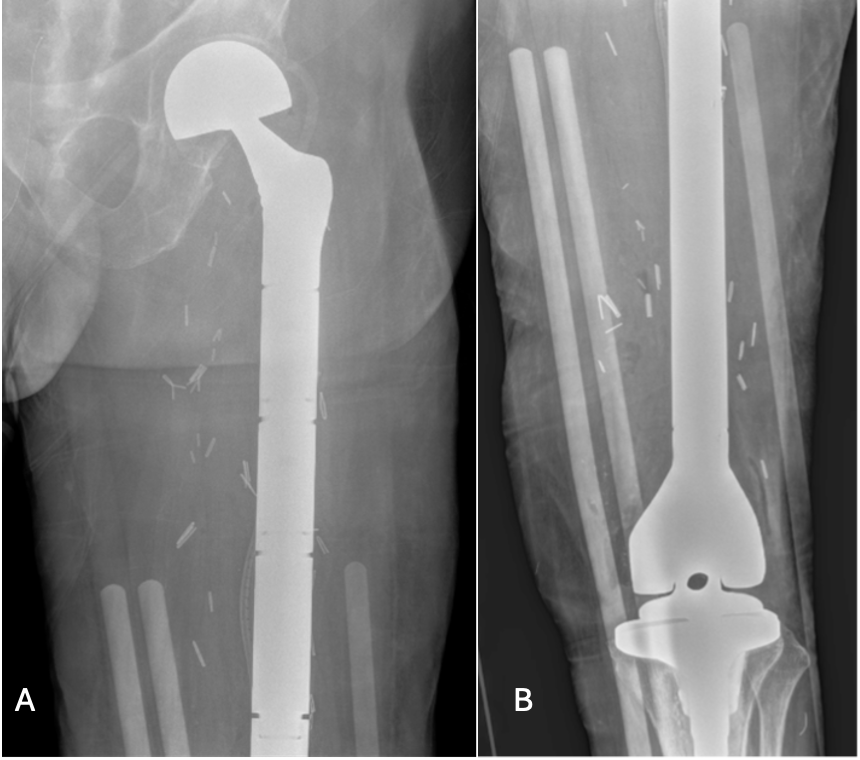

Treatment and management. Following initial fixation, progressive disease prompted a proximal femur replacement, which was later converted to a total femur arthroplasty (Figure 6) due to distal extension and sarcomatous transformation. He was referred to radiation oncology for radiation therapy, with the first session in August 2024, and the therapy was completed in September 2024.

Figure 6A-B. Plain radiograph of left femur. Postsurgical changes of left femur resection with megaprosthesis placement and articulating tibial component.